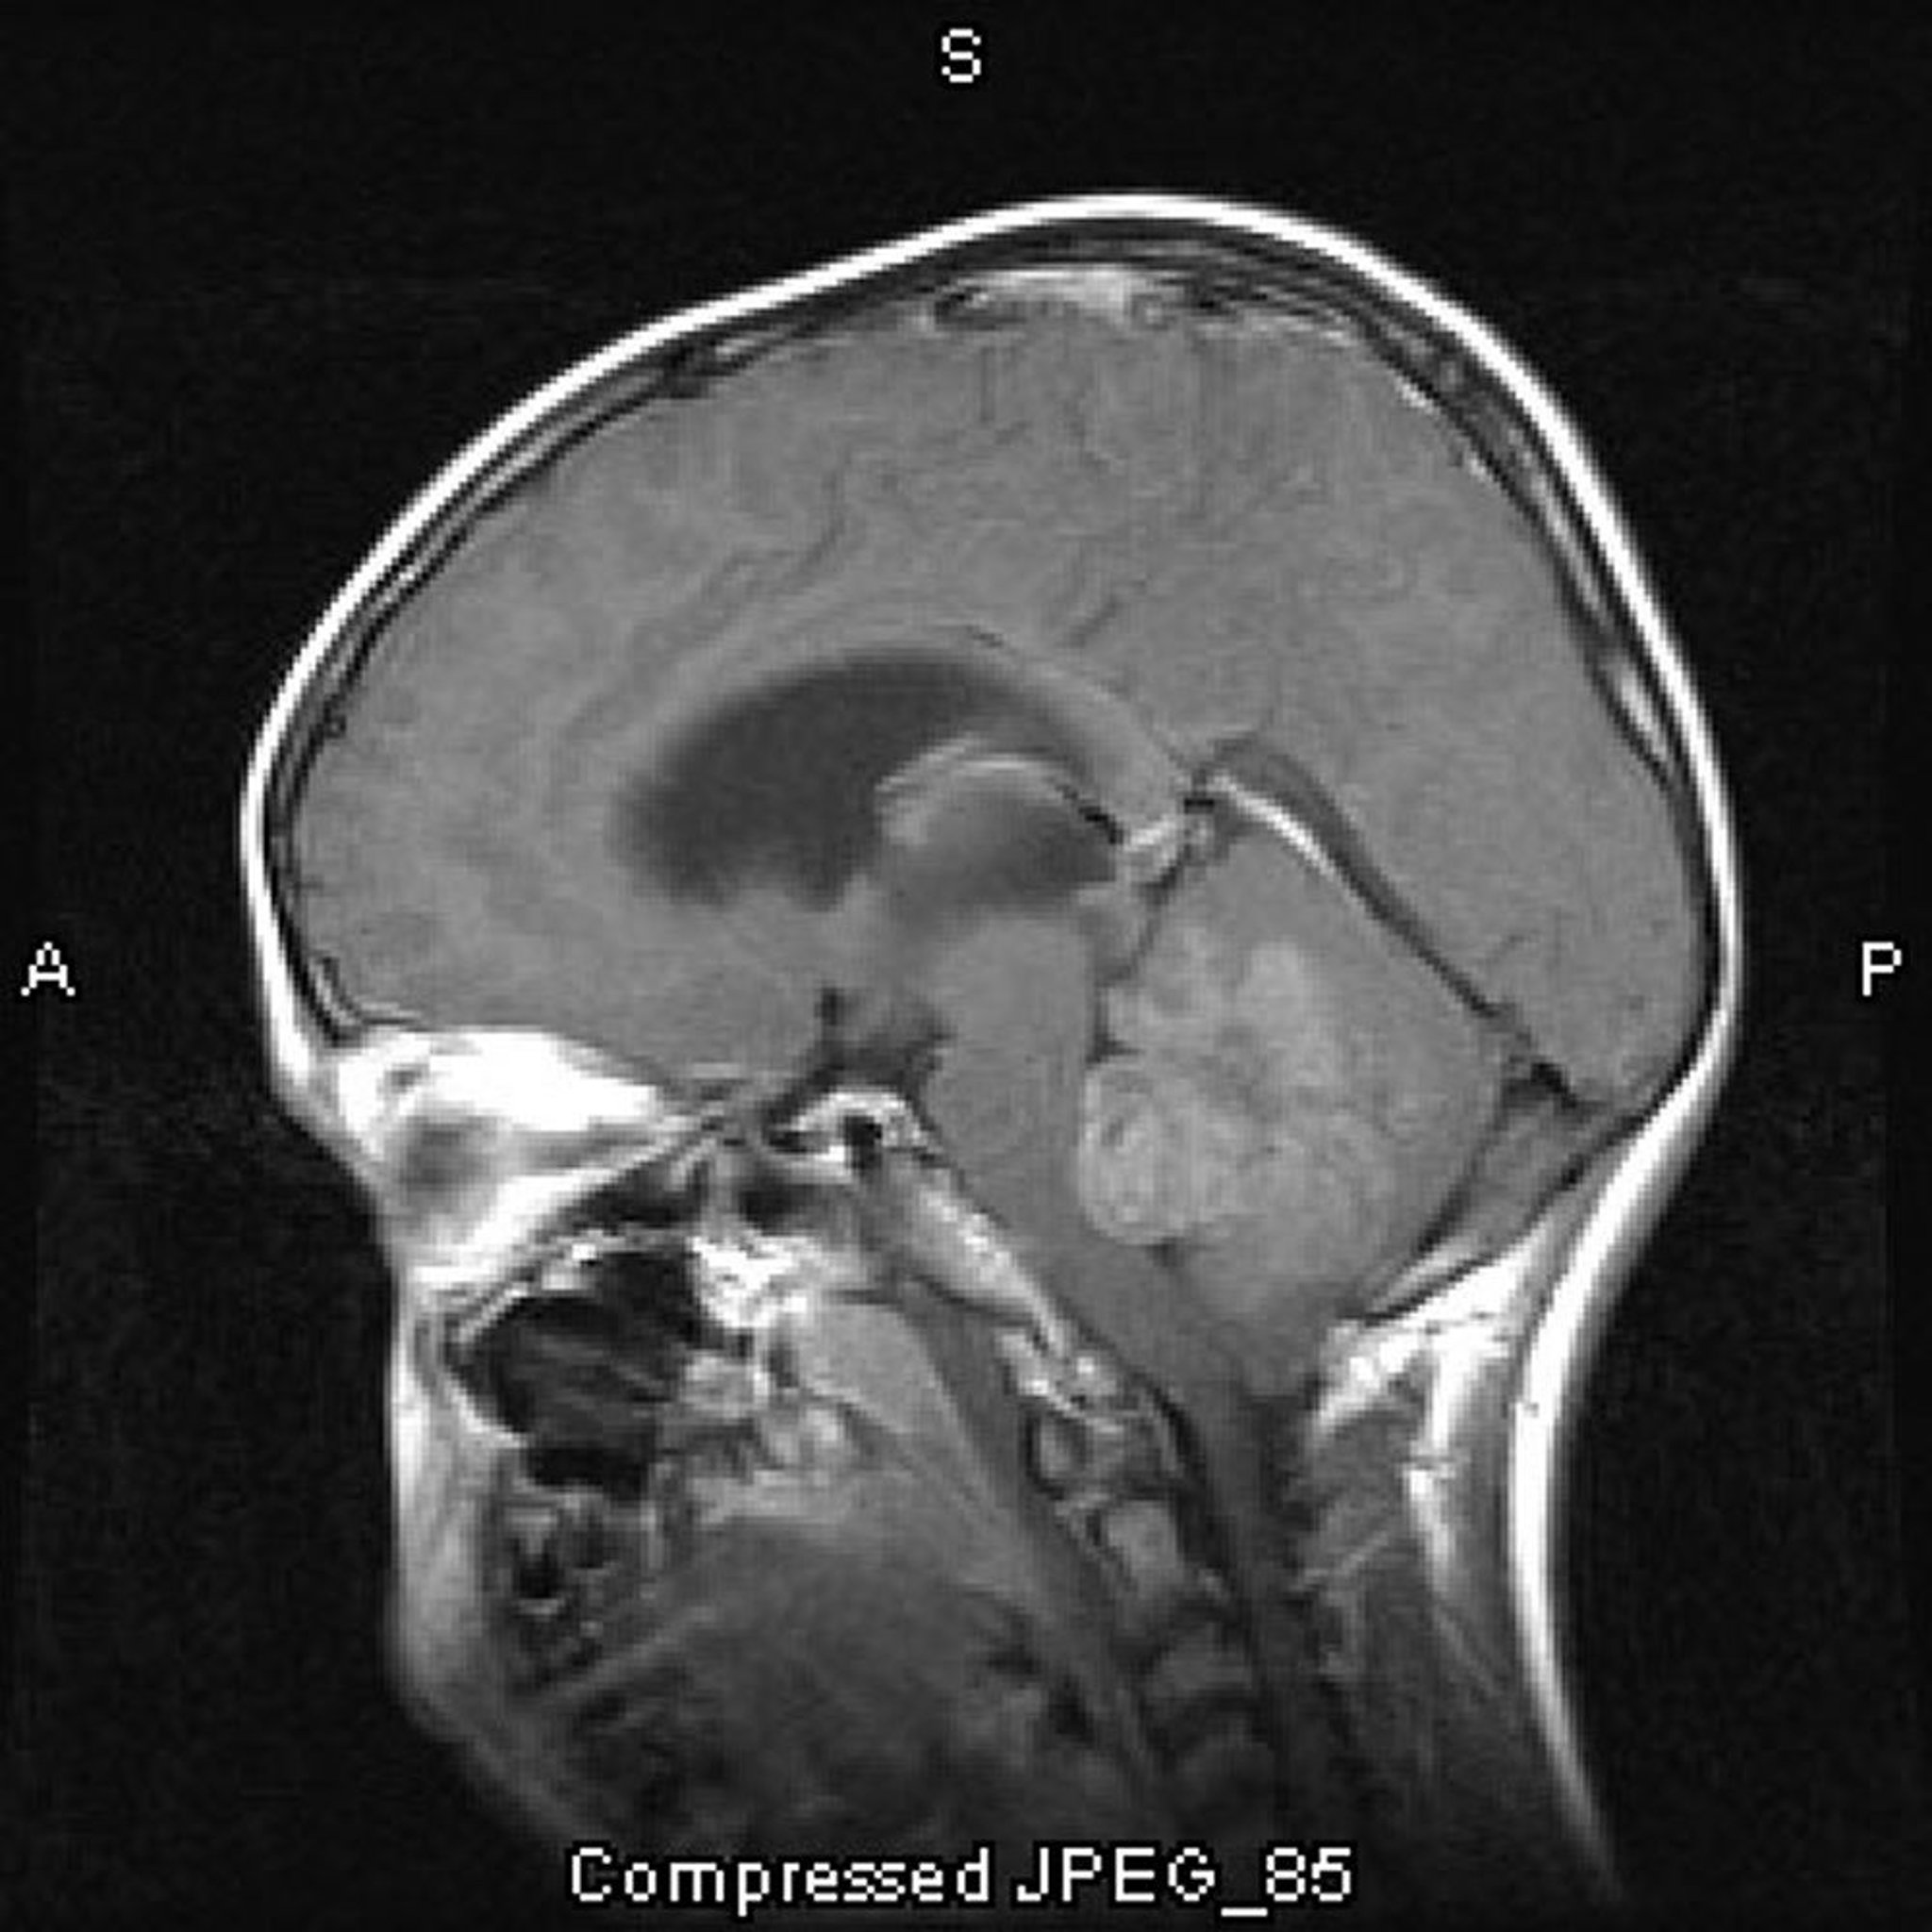

Médulloblastome

Cette IRM avec injection de produit de contraste montre un médulloblastome qui se développe dans le toit et obstrue le 4e ventricule.

Image courtoisie de William R. Shapiro, MD.